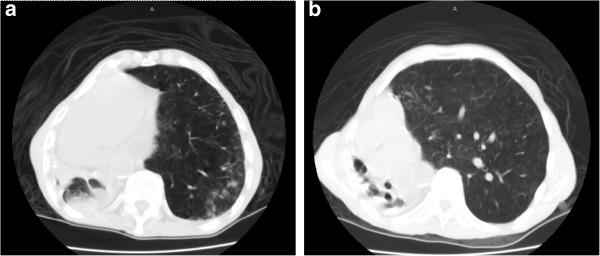

Postpneumonectomy syndrome is a rare condition that is characterized by dyspnea resulting from an extreme mediastinal shift and bronchial compression of the residual lung following surgical pneumonectomy. It is even rarer for this syndrome to present in patients without a history of prior lung surgery but induced by autopneumonectomy due to parenchymal disease, an entity termed 'postpneumonectomy-like syndrome'.

We present a rare case of a 91-year-old Puerto Rican man presenting with progressively worsening dyspnea with a history of pulmonary tuberculosis diagnosed 40 years earlier who developed severe unilateral lung fibrosis. Plain X-ray and computed tomography scans confirmed the presence of postpneumonectomy-like syndrome secondary to his parenchymal lung destruction. The patient developed cor pulmonale due to his extensive lung disease and as a consequence was not a suitable candidate for surgical intervention. The patient was otherwise stable until he developed acute respiratory distress from an acute upper gastrointestinal bleed and died four days into his hospital course.